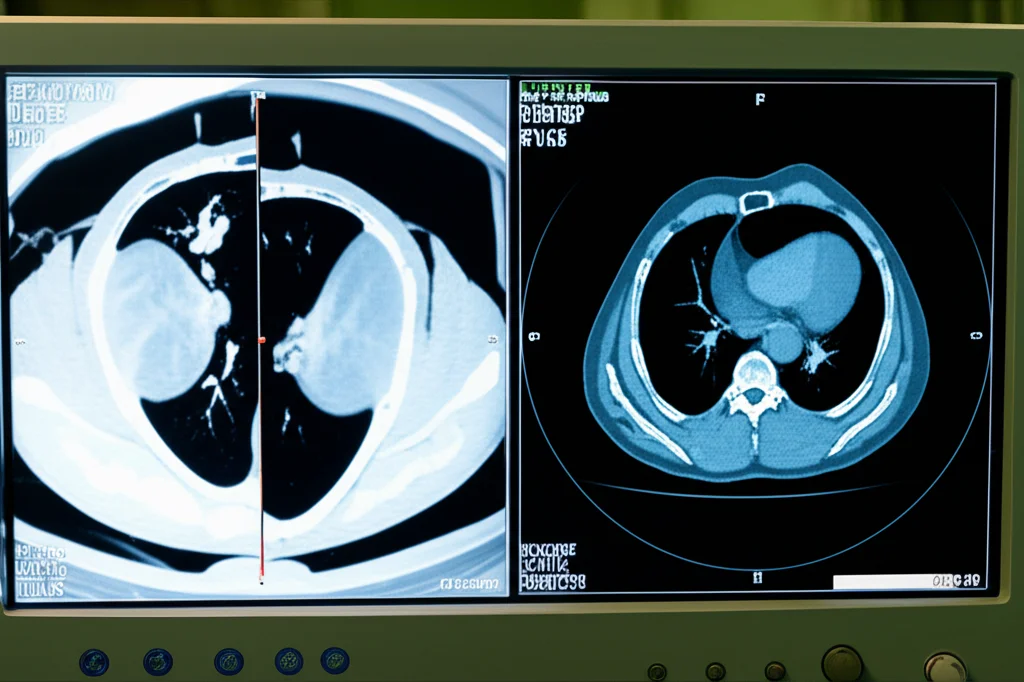

So, let’s talk about something pretty important in the world of medical imaging, specifically for folks dealing with Neuroendocrine Neoplasms, or NENs. If you’re not familiar, these are a group of tumors that often overexpress a thing called the somatostatin receptor (SSTR). And that’s where PET/CT scans using somatostatin analogues (SSAs) come in – they’re a cornerstone, a real big deal, in managing these patients.

For a while now, the go-to, the “gold standard” if you will, has been [68Ga]Ga-DOTA-SSA PET/CT. It’s been revolutionary, no doubt about it, helping doctors see and manage NENs like never before. But, like anything, it’s got its quirks. We’re talking high costs, generators that aren’t always easy to come by, a short tracer half-life (meaning you can only scan a few patients per batch), and a positron energy that can sometimes fuzz up the spatial resolution a bit.

One specific tracer, [18F]AlF-NOTA-octreotide (or [18F]AlF-OC for short), has been looking really promising. It’s got all those lovely fluorine-18 advantages and can be made using a standard, automated method. Early studies comparing it to the gallium-68 tracers showed similar safety and how it moves through the body.

So, we took a look at the data from that same multicenter trial. We had 75 NEN patients who got *both* a [68Ga]Ga-DOTA-SSA scan (mostly DOTATATE, some DOTANOC) and an [18F]AlF-OC scan within about a month of each other. Five readers – a mix of experienced nuclear medicine physicians and one in training – independently reviewed the masked images. They looked for lesions, characterized them (was it benign? probably malignant? somewhere in between?), counted them, and scored how visible they were (conspicuity) using a 5-point scale. They also scored the overall image quality and something called the Krenning score, which helps decide if a patient might be a good candidate for therapy.